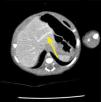

The newborn was admitted asymptomatic, in good general condition, ruddy, hydrated, and vital signs within normal values. Clinical examination showed no evidence of microcephaly or shortening of the long bones observed in obstetric ultrasound. The investigation continued with: (1) abdominal ultrasound, which showed no change, with insufficient assessment of portal vein; (2) computerized tomography (CT) angiography, which indicated liver with normal dimensions, contours, and density, with prominence of the left portal vein branch, up to the periphery of the left lateral segment, where it was observed vascular dilation and prominence of the adjacent left hepatic vein, with resemblance of intrahepatic portosystemic shunt on the left lateral segment of the liver (Fig. 1); (3) Abdominal ultrasound with Doppler, which showed prominences of the portal vein right and left branches, with anomalous path of right portal vein, with posterior-superior direction, communication signs between the portal vein and the middle hepatic vein, the site with increased peak systolic velocity and oscillating flow, suggestive of portosystemic shunt (Fig. 2). Because of the association of the shunt with other diseases and complications other tests were performed: normal electroencephalogram, normal echocardiogram, laboratory tests (Table 1).